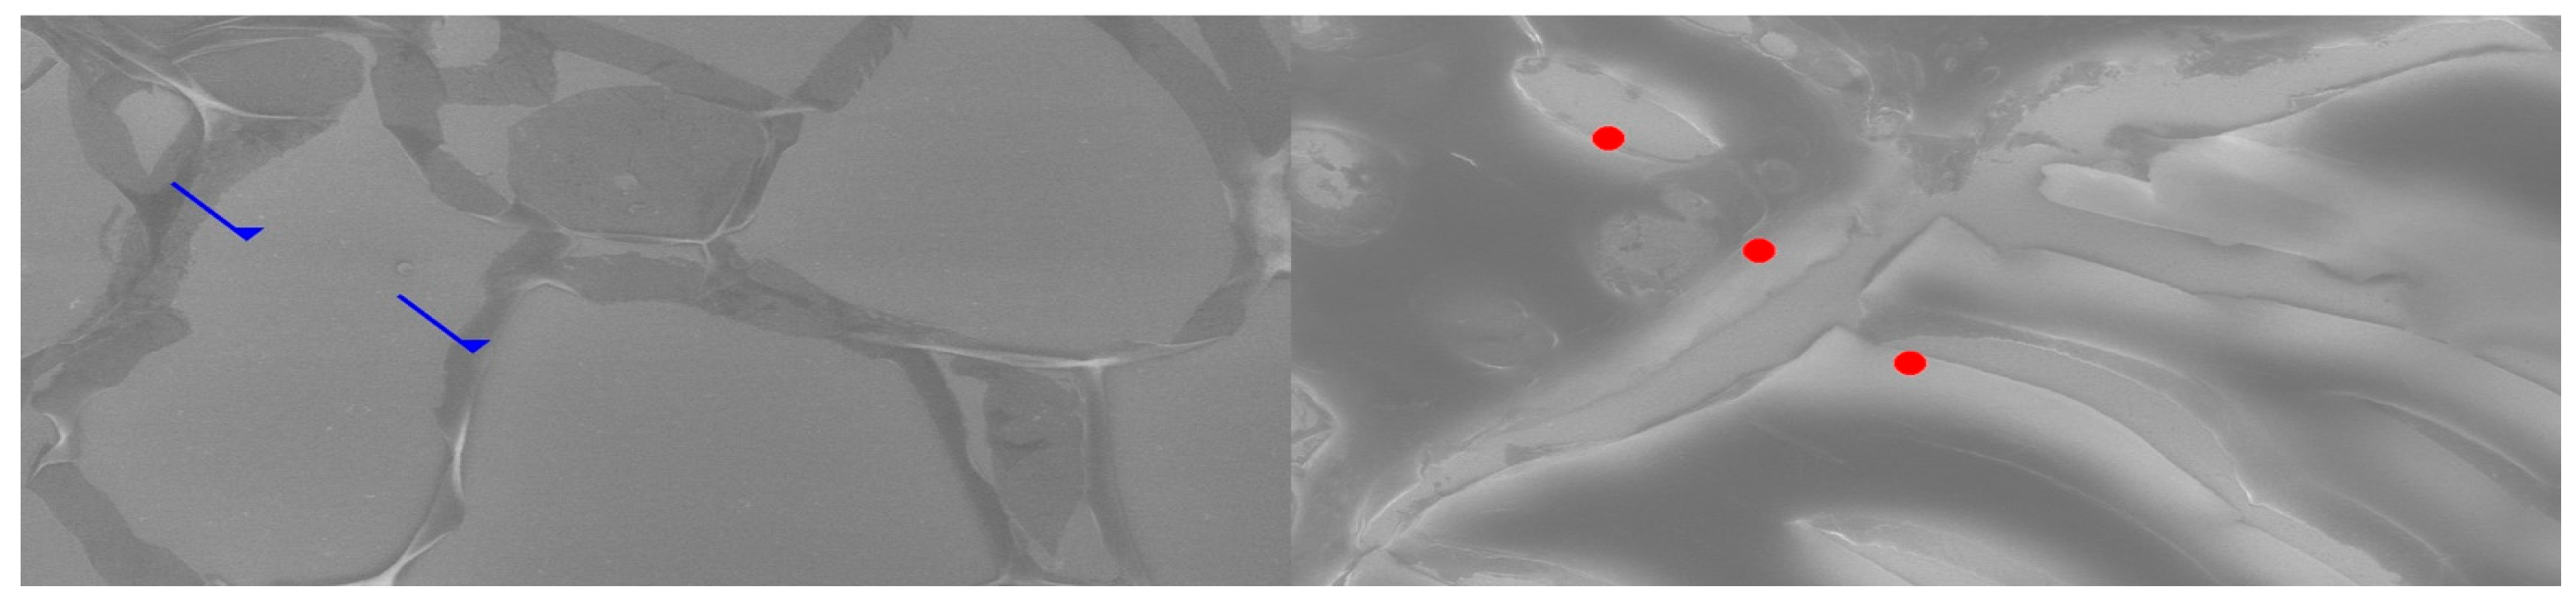

2.3. Results of the SEM Study

Comparative SEM examination at ×1000 magnification revealed striking morphological parallels between thymus and parathyroid tissue. In thymic samples, the stromal scaffold was traversed by fine vascular grooves and channels, consistent with the capillary meshwork required for thymocyte maturation. Although less prominent, parathyroid sections displayed surface depressions and intercellular clefts suggestive of similar microvascular pathways, indicating that both glands may share comparable patterns of vascular organization. At the stromal level, the thymus exhibited a reticular epithelial network with interlacing bridges forming a three-dimensional scaffold, while the parathyroid presented clusters of chief cells with distinct membrane contours and discrete intercellular connections.

Certain parathyroid areas even displayed reticular-like meshes, reminiscent of the thymic scaffold and suggestive of structural convergence. In addition, concentric epithelial whorls typical of Hassall’s corpuscles were readily identified in thymic tissue, whereas the parathyroid revealed focal stromal nodules with partially lamellar arrangements, not identical but evocative of concentric condensations and consistent with the possibility of shared embryonic remnants.

Further similarities were observed at the level of cell surface specialization. Thymic epithelial cells exhibited microprojections and membrane folds that expanded the contact surface for intercellular communication, while parathyroid chief cells displayed less dense but clearly identifiable microvillous projections. Such surface domains provide morphological support for the immunohistochemically demonstrated localization of receptors, including Thymosin and PTH1R.

Age-related differences were also noted: the thymic architecture appeared relatively preserved, with dense stromal and cellular organization, whereas the parathyroid showed mature chief cell fields with limited fibrous encapsulation, yet still retained organizational echoes of the thymic pattern. These ultrastructural observations highlight shared microvascular reliefs, convergent stromal frameworks, analogies to Hassall’s corpuscles, and comparable microvillous surface domains. Collectively, they reinforce the hypothesis that the thymus and parathyroid are not merely embryological neighbors but functionally interconnected glands, potentially linked through a parathyroid–thymus possible portal system (Figure 5 and Figure 6).

Figure 6. Comparative SEM analysis of thymus (left) and parathyroid (right) at ×1000 magnification. In the left panel blue arrows indicate concentrically arranged stromal structures resembling Hassall’s corpuscles. In the right panel, red bullets highlight cell surface specializations (microvilli-like projections and membrane protrusions) suggestive of receptor docking domains. These ultrastructural similarities provide morphological support for the proposed parathyroid–thymus functional interconnection.